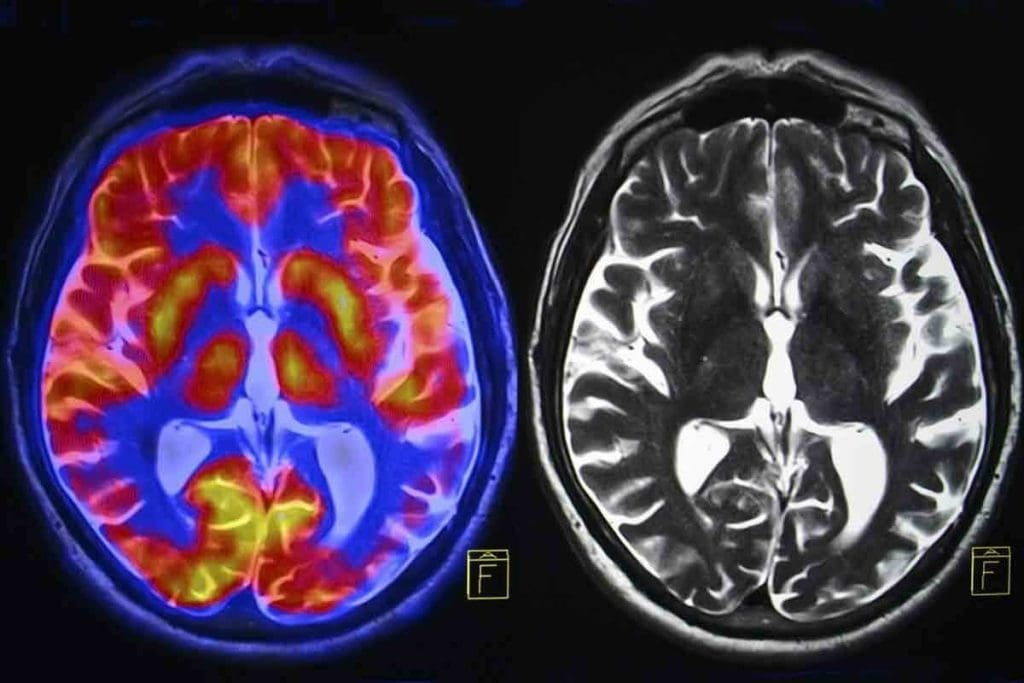

CT scanning is key in finding and checking on brain masses. It uses X-rays to make clear images of the brain. This tech helps us make accurate diagnoses and plan treatments for brain mass patients.

CT scans find brain masses by using X-rays that pass through tissues differently. Detectors catch these changes and make images that show tissue density differences. These images help us spot masses and understand their details.

CT scans play a big role in checking brain tumors. They help us see how dense the tumor is and how it reacts to contrast. We look for specific signs to figure out what kind of tumor it is.

The density of a tumor on a CT scan is key. It tells us if the tumor is more or less dense than the normal brain. Some tumors are darker because they have fewer cells or more fat. Others are brighter because they have more cells or calcium.

When we give the patient contrast, we see how the tumor reacts. This tells us about the tumor’s blood flow and how well it blocks blood flow to the brain. The way the tumor looks after contrast can hint at its type and how serious it is.